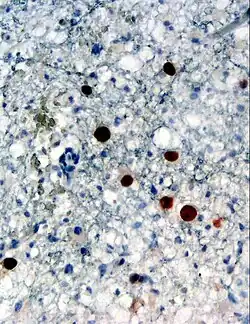

| Immunohistochemical detection of Human polyomavirus 2 protein (stained brown) in a brain biopsy (glia demonstrating progressive multifocal leukoencephalopathy) | |